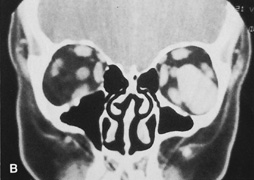

Magnetic resonance imaging is useful in selected cases, especially when evaluating the orbital cranial junction. Significant bony artifact and a lack of orbital fat in the orbital apex make CT scan resolution of the orbital apex structures poor. Because cortical bone has low signal on MRI, there is no bone artifact when viewing the orbital apex on MRI. The lack of intervening fat in the apex to provide contrast is overcome on MRI because contrast is provided by the individual nuclear characteristics of each tissue so that the orbital apex structures are visualized well. Consequently, conditions that affect the optic nerve and chiasm, such as optic nerve meningioma and glioma, generally are evaluated with MRI rather than CT scan (Fig. 2).

Fig. 2. A. Axial orbital CT scan of right optic nerve meningioma. Note lack of detail in orbital apex. B. Axial orbital MR image, same patient. Note increased detail in orbital apex owing to lack of bone artifact. C. MRI with gadolinium contrast. Note extension into brain not easily appreciated with CT scanning or MRI without contrast.

Use of a contrast agent such as gadolinium can further enhance the T1 signal intensity of lesions and is particularly helpful in imaging areas where there has been a breakdown in the blood–brain barrier. Because orbital fat produces a bright signal on T1-weighted images, orbital MR usually is performed with “fat suppression” to prevent masking of lesions. However, incomplete fat suppression can produce artifacts that may be misinterpreted as abnormal enhancement.